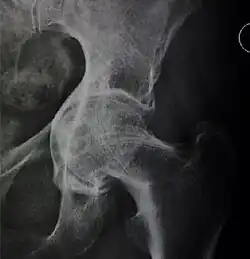

![Figure 5 (b). Coxa profunda.[3]](./_assets_/X-ray_of_coxa_profunda.jpg)

![Figure 5 (c). Protrusio acetabuli.[3]](./_assets_/X-ray_of_protrusio_acetabuli.jpg)

Measurements

- Fossa/ilioischial relationship: In normal conditions the floor of the acetabular fossa is lateral to the ilioischial line by 2 mm in men and 1 mm in women. When the acetabular floor overlaps or overpasses the ilioischial line, the diagnosis of coxa profunda can be made. Nevertheless, coxa profunda had been found in 76% of asymptomatic hips, mainly in women. Therefore, this as an isolate criterion is not enough to make the diagnosis of pincer-type impingement. A more severe condition is protrusio acetabuli, diagnosed when the femoral head overlaps or overpasses the ilioischial line.[3]